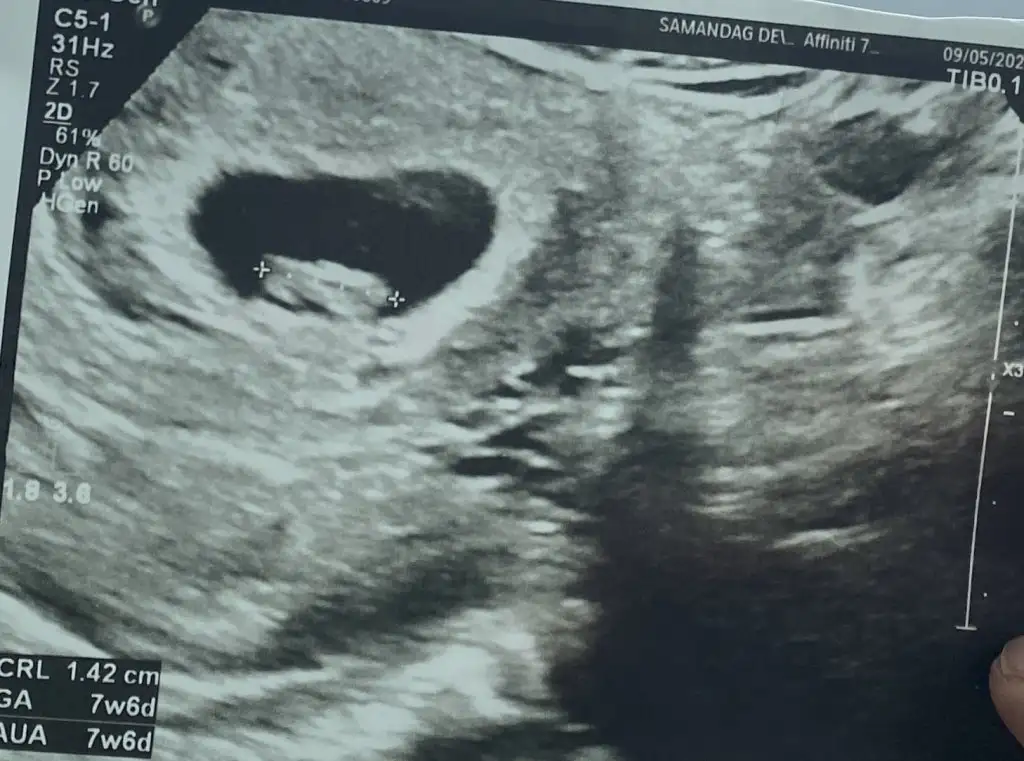

Seninki yer değiştirmeye hazırlanıyor sankiEki Görüntüle 3425141

Ya benimki zaten ilk bir görünmedi kadın bi tuttu boş, kalbime indi. Sonra baktım bi dolanan bişiler var ordaSeninki yer değiştirmeye hazırlanıyor sankiHem zaten hem aynı yerde mi duracaklar ki bir dahaki sefere diğer tarafta görünme ihtimali yok mu dhskdsl

Gezmeye çıkmış kız ne var siz de hemen kovalamışsınız çocuuYa benimki zaten ilk bir görünmedi kadın bi tuttu boş, kalbime indi. Sonra baktım bi dolanan bişiler var orda

Ayy kesenin şekline göre erkekBenimkini de tahmin etsenize